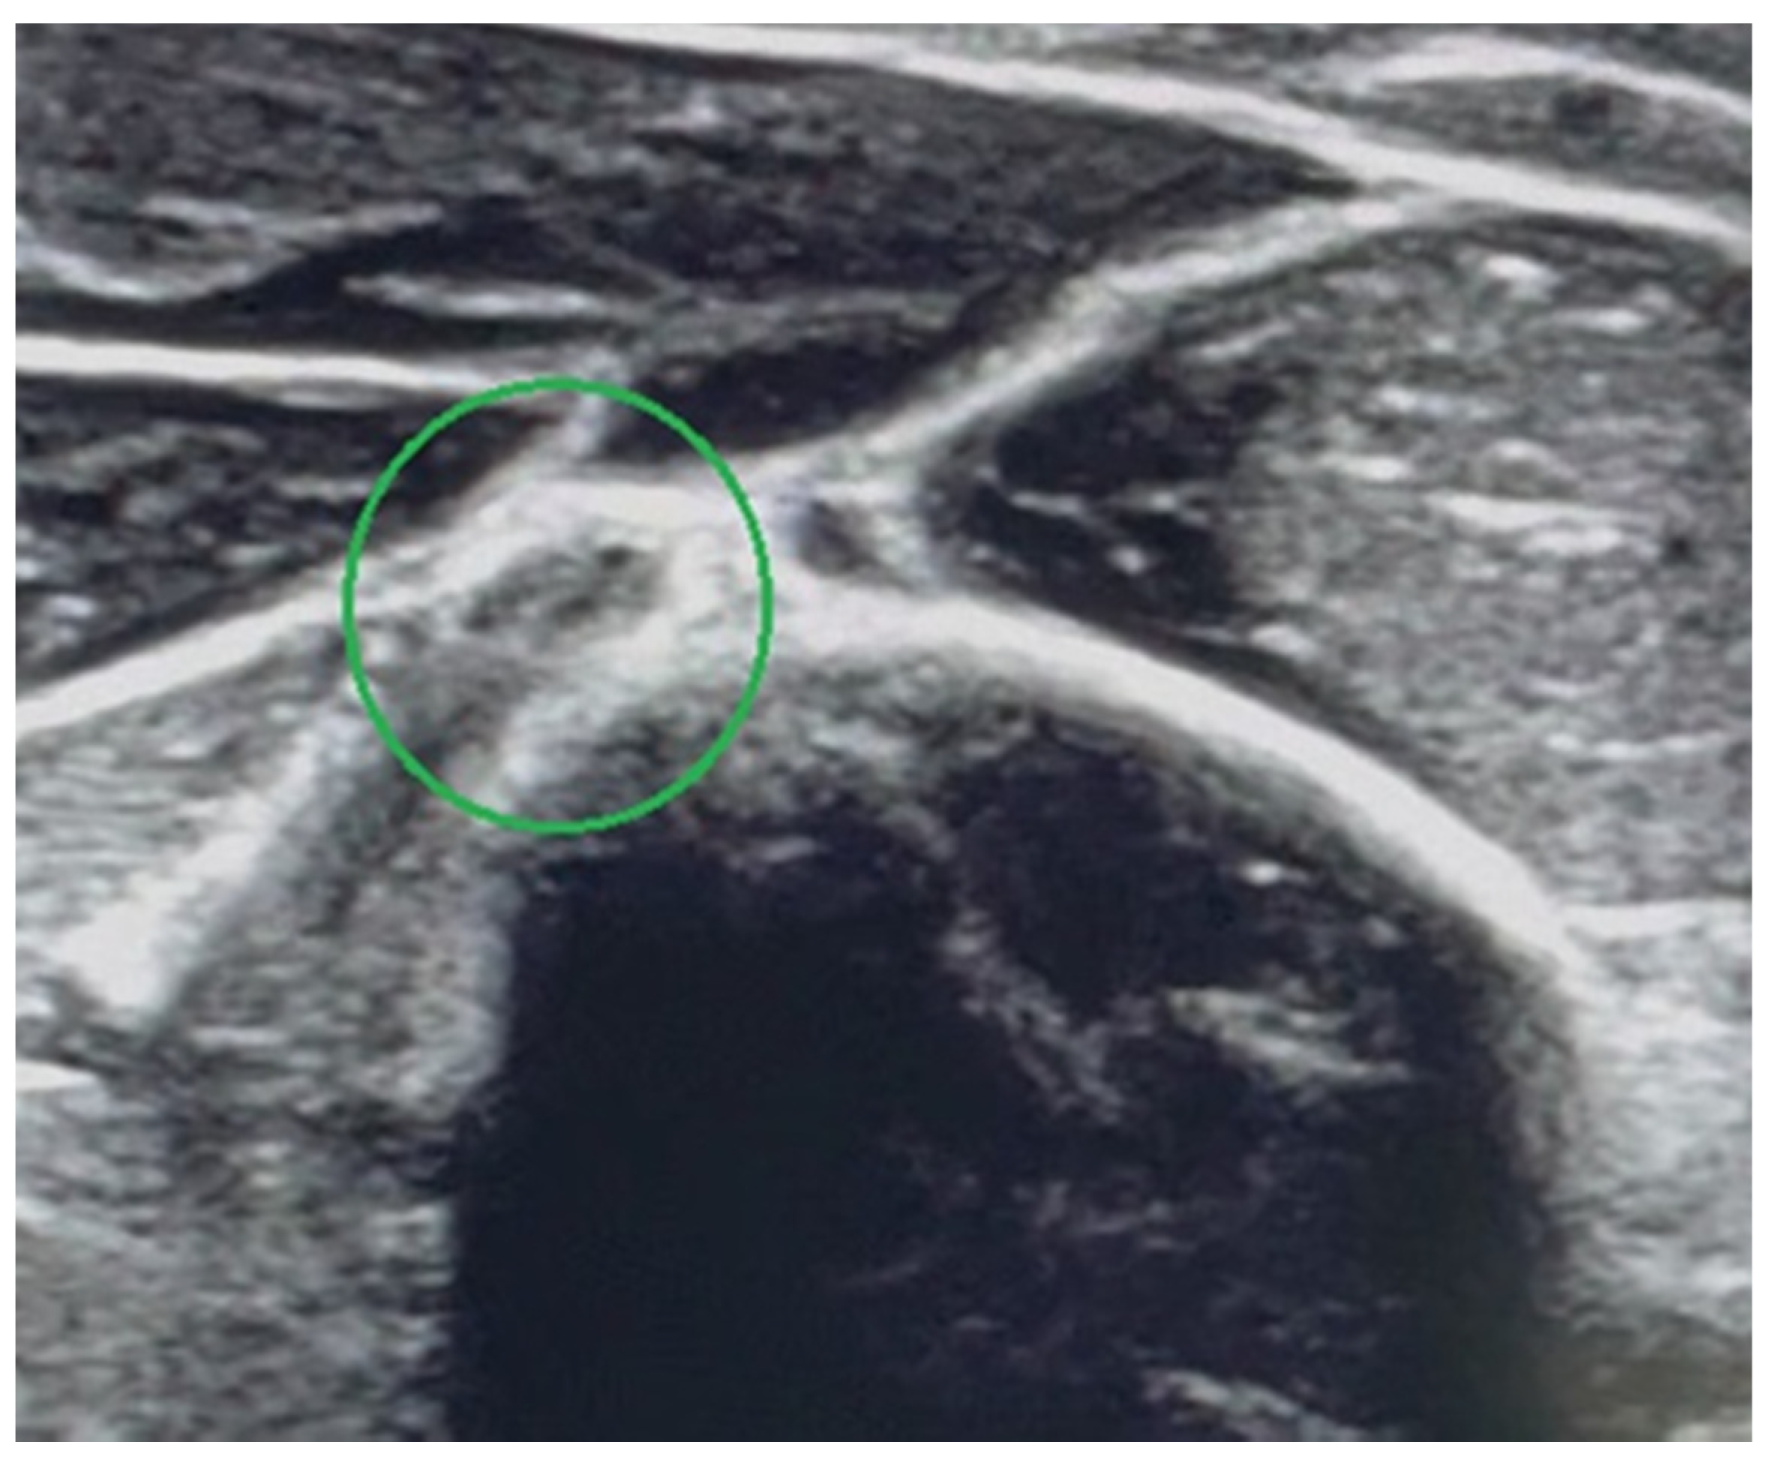

4.2. Ultrasound Examination